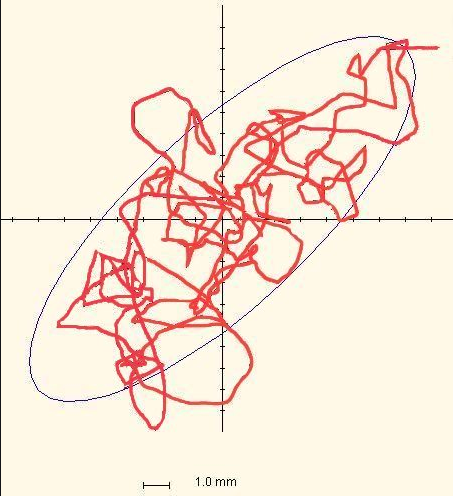

Lo Sway Test consiste nell’analisi del movimento del centro operativo di massa ( C.O.M.) di un soggetto in posizione eretta per un periodo determinato di tempo, solitamente 30 secondi o 60 secondi. L’analisi viene eseguita attraverso l’utilizzo di un sistema inerziale (composto da accelerometri, giroscopi e magnetometri) posizionato all’altezza delle scapole, che permette di tracciare gli spostamenti del centro di massa nello spazio ed analizzarne distanza percorsa, velocità ed accelerazione.

Alcune variabili chiave, che possono dare un’indicazione precisa su quello che è il grado di stabilità del soggetto, sono:

- l’area delineata dal movimento del centro di massa nello spazio (o area del gomitolo)

- la distanza percorsa in oscillazione medio-laterale

- la distanza percorsa in oscillazione antero-posteriore

- le frequenze e velocità di tali oscillazioni.

Queste variabili forniscono già una buona panoramica, oltre che del grado di stabilità dell’individuo, anche della strategia di controllo posturale messa in atto. Se consideriamo infatti le due principali direzioni di movimento, possiamo notare come, in soggetti sani, la maggior parte dell’oscillazione avvenga sul piano antero-posteriore (Horak, 1987).